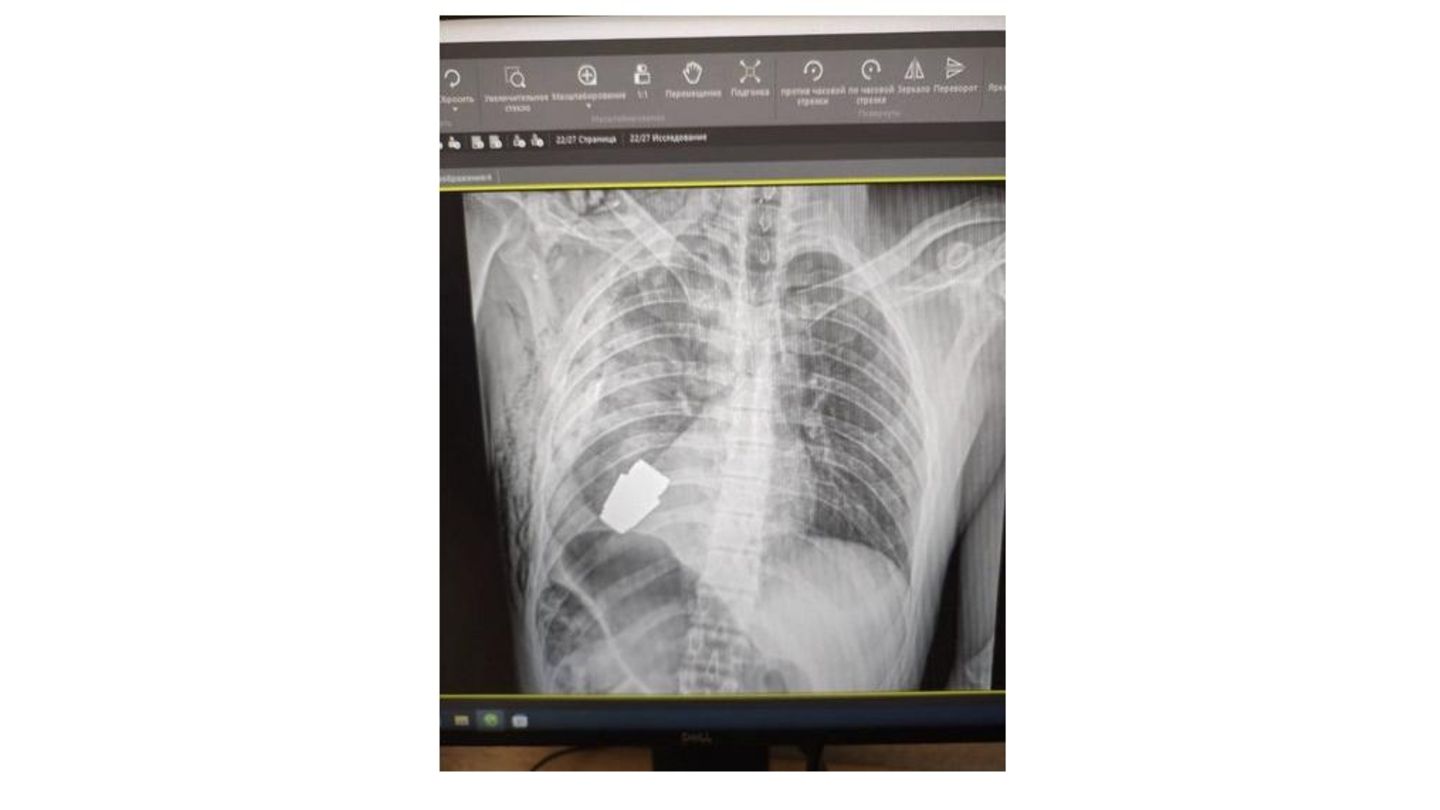

Die Operation war heikel, aber ein voller Erfolg. Ein ukrainischer Militärarzt musste den Brustkorb eines Soldaten öffnen, weil sich darin eine nicht explodierte Splittergranate befand.

In der Ukraine macht derzeit eine spektakuläre Kriegs-Operation Schlagzeilen. Militärchirurgen mussten einem Soldaten eine nicht explodierte Granate aus der Lunge entfernen, wie das Kommando der ukrainischen Sanitätskräfte berichtet. Die Waffe wurde von einem Granatenwerfer abgefeuert, drang in die Brust des Kämpfers ein, explodierte aber nicht.

"Die OP wurde von einem der erfahrensten Chirurgen der Streitkräfte der Ukraine, Generalmajor Andrii Verba, durchgeführt", heißt es in dem Beitrag, der auf Facebook veröffentlicht wurde. Und, wie die Armeeführung betont, "ohne den Einsatz von Elektrokoagulation, da die Granate jeden Moment explodieren könnte“, wie es weiter heißt. Mit der Wechselstrom-Methode wird üblicherweise Gewebe entfernt oder zerschnitten.

Die stellvertretende Verteidigungsministerin Hanna Malyar sagte dazu: "Die Granate wurde in Anwesenheit von zwei Pionieren entfernt, die für die Sicherheit des medizinischen Personals sorgten." Der Eingriff verlief erfolgreich und der Soldat erholt sich nun.